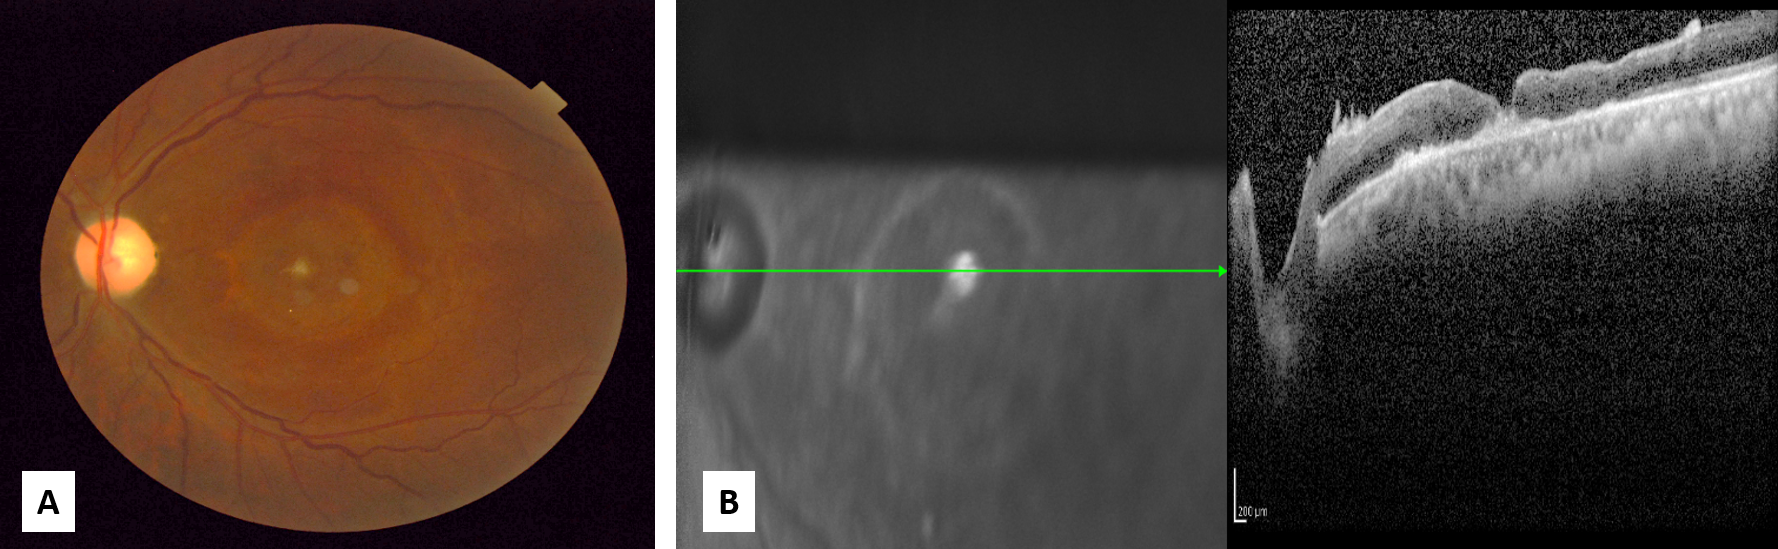

How to detect a macular hole?

We are able to detect a macular hole during an eye examination. Sometimes, a special scan of the back of the eye (Optical Coherence Tomography) may be needed to confirm the presence of a macular hole. If a macular hole is present, your surgeon will likely recommend a surgical procedure to try to close the hole and improve your vision. Surgery is the only way to treat a macular hole, there are no eye drops or medications that you can take that will help.